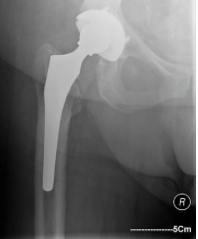

What are the signs of uncemented implant failure?

What are the complications of uncemented prosthesis?